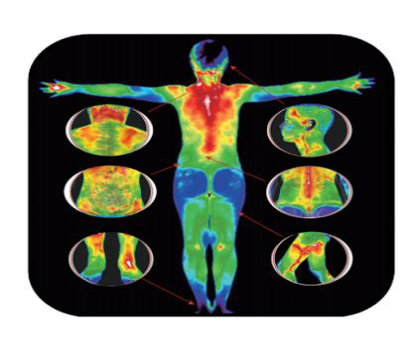

近期,广东省第二人民医院(以下简称“省二医”)疼痛科引入了红外热像检查系统,能够快速准确探测到目标物的温度变化情况,并将其转化为温度值图像,再通过专业的图像分析工具,帮患者把疼痛感受客观“描述”出来,在不接触、无辐射的情况下使疼痛形象化,大大提高诊断的准确率和治疗的有效率!

2.全面、快捷:全身情况图像采集仅需3-5分钟,即时进行健康分析;

3.早期预警:许多疾病在早期,只有功能性(代谢)改变而没有形成器质性病变,温变早于病变,功能变化早于病理变化。红外热像检查系统可以在机体没有明显症状的情况下解读出隐患,更早地发现问题;

4.高敏感度:能极其敏感地接收人体细胞新陈代谢所产生的热辐射(小于0.025 ℃ ),显示人体内异常热源的分布、深度、强度、形态及走势;